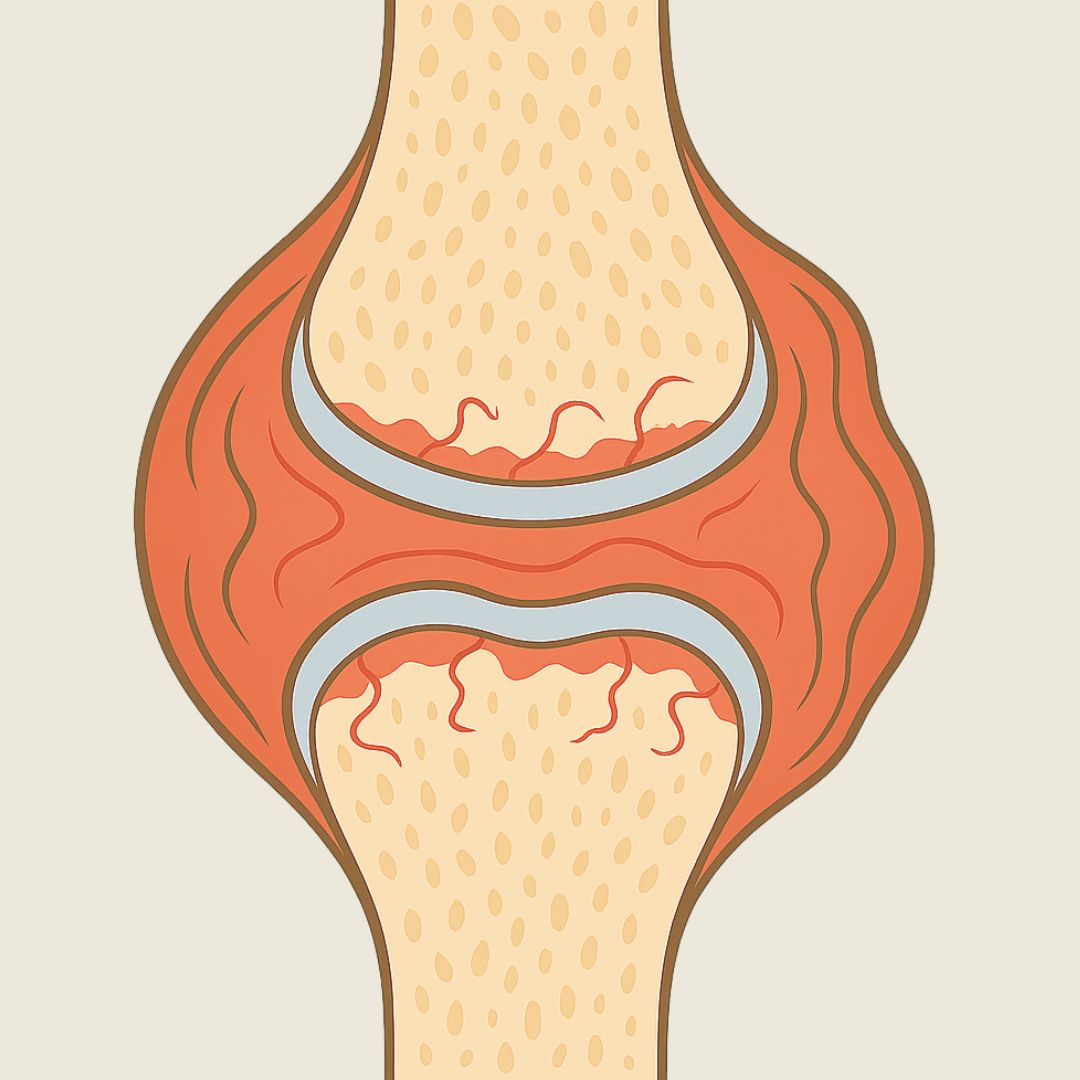

Inflammation Sets In

Irritation in the joint lining leads to swelling, discomfort, and stiffness.

How Billie's helps: Packed with natural anti-inflammatory ingredients such as Turmeric and Vitamin C to help soothe irritation and reduce inflammation.

Bone Rubs On Bone

With cartilage worn away, bones start grinding directly against each other, causing further damage and pain.

How Billie's helps: Formulated to slow down cartilage breakdown, helping to prevent bone-on-bone friction and further joint damage.